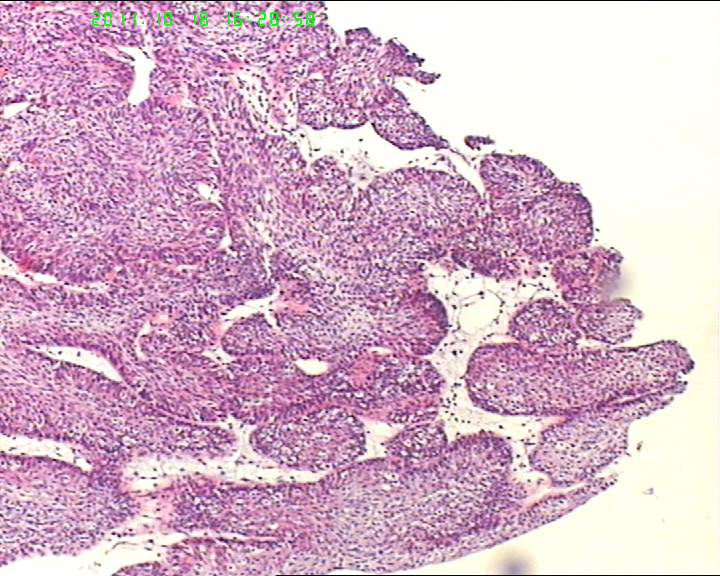

70岁女性体检发现膀胱肿物,是癌吗?

膀胱后壁一2*1cm大小肿物